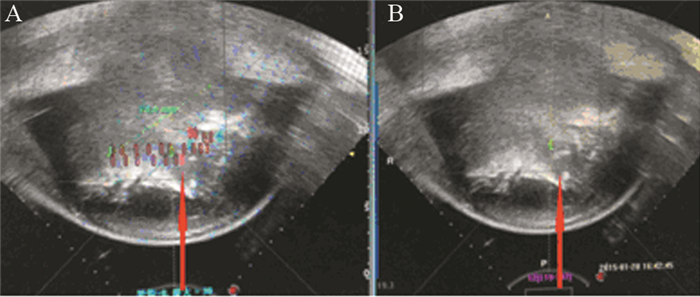

治疗后患者左肩可自由活动,疼痛明显减轻,疼痛VAS评分0~2分,舒乐安定再次减半,每晚0.5 mg口服,奥施康定减量,每12 h 10 mg镇痛治疗。治疗前后的影像学变化见图 1、2。

| 图 2 第2次HIFU治疗前 (A) 后 (B) 的术中影像学变化 Figure 2 Intraoperative imaging changes before (A) and after (B) the second HIFU treatment |